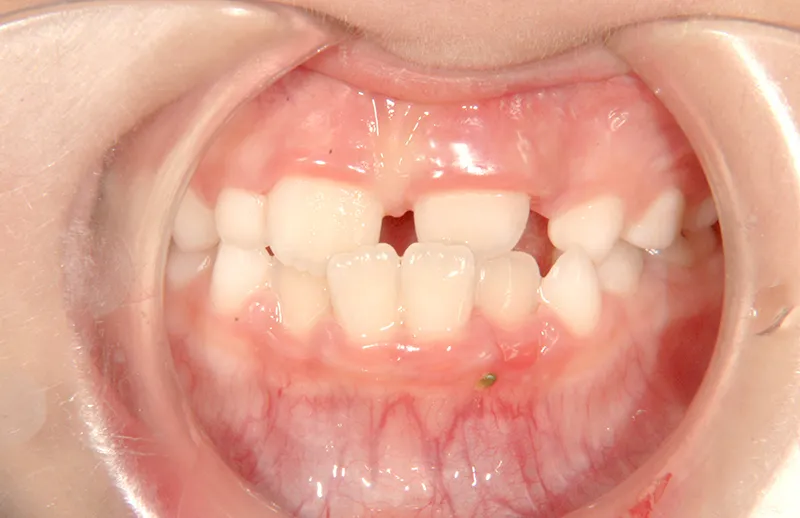

• 初診

初診時年齢 小学校1年生 (男性) 主訴 すきっ歯・ガタガタ・受け口

診断名 叢生・反対咬合・空隙歯列 装置名

拡大床

特徴 ゆがんで生えている

状態 永久歯が生える隙間がない(叢生)

受け口(下顎前突/反対咬合)

すきっ歯(空隙歯列)

上の前歯が下の前歯より後ろに入って、受け口になっています。

下の歯は永久歯の生えるスペースがないので、オリジナル矯正装置で受け口を治して、永久歯の生えるスペースを作りました。

初診